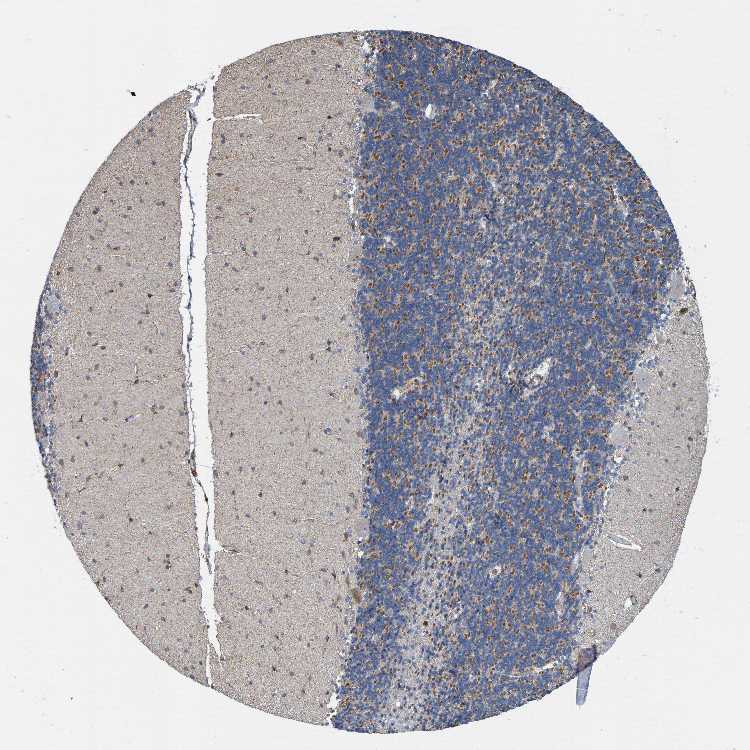

CEREBELLUM - Antibody stainingi

Antibody staining in the annotated cell types in the current human tissue is reported as not detected, low, medium, or high, based on conventional immunohistochemistry profiling in selected tissues. This score is based on the combination of the staining intensity and fraction of stained cells.

Each image is clickable and will lead to virtual microscopy that enables deeper exploration of all samples and also displays staining intensity scores, fraction scores and subcellular localization as well as patient and tissue information for each sample.

Antibody HPA004182Antibody HPA022903Antibody CAB018621

Purkinje cells Not detectedMedium-

Cells in granular layer Not detectedMediumLow

Cells in molecular layer Not detectedMediumLow